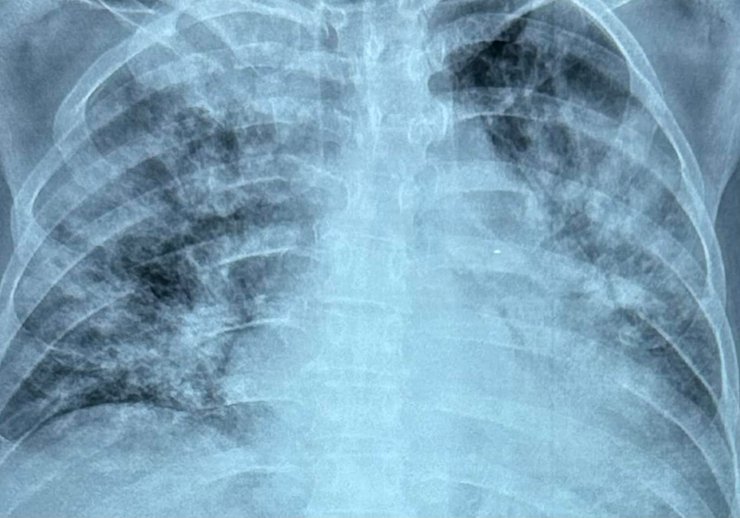

поражение легких

Тяжелое поражение легких у больной 35 лет. Смерть на 8-й день заболевания.